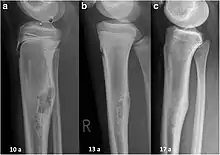

The most common bone tumor is a non-ossifying fibroma.[4] Average five-year survival in the United States after being diagnosed with bone and joint cancer is 67%.[5] The earliest known bone tumor was an osteosarcoma in a foot bone discovered in South Africa, between 1.6 and 1.8 million years ago.[6]